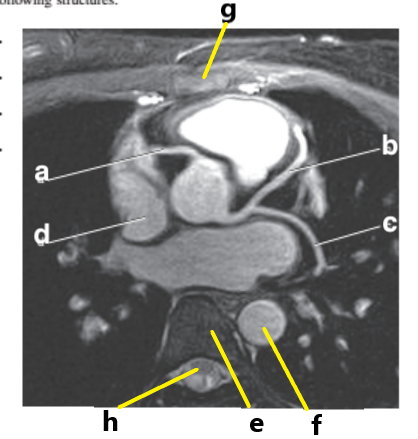

Which letter is the Pulmonary trunk ?

d

What is letter b ?

Left ventricle

What is behind letter e ?

What is letter a ?

Left atrium

Right ventricle

What is letter h ?

What is letter d ?

Ascending aorta

Which letter is the Right coronary artery ?

c

What is letter g ?

Right atrium

Pulmonary trunk

Left anterior descending artery

Bicuspid valve / LT AV valve

Descending thoracic aorta

Aortic arch